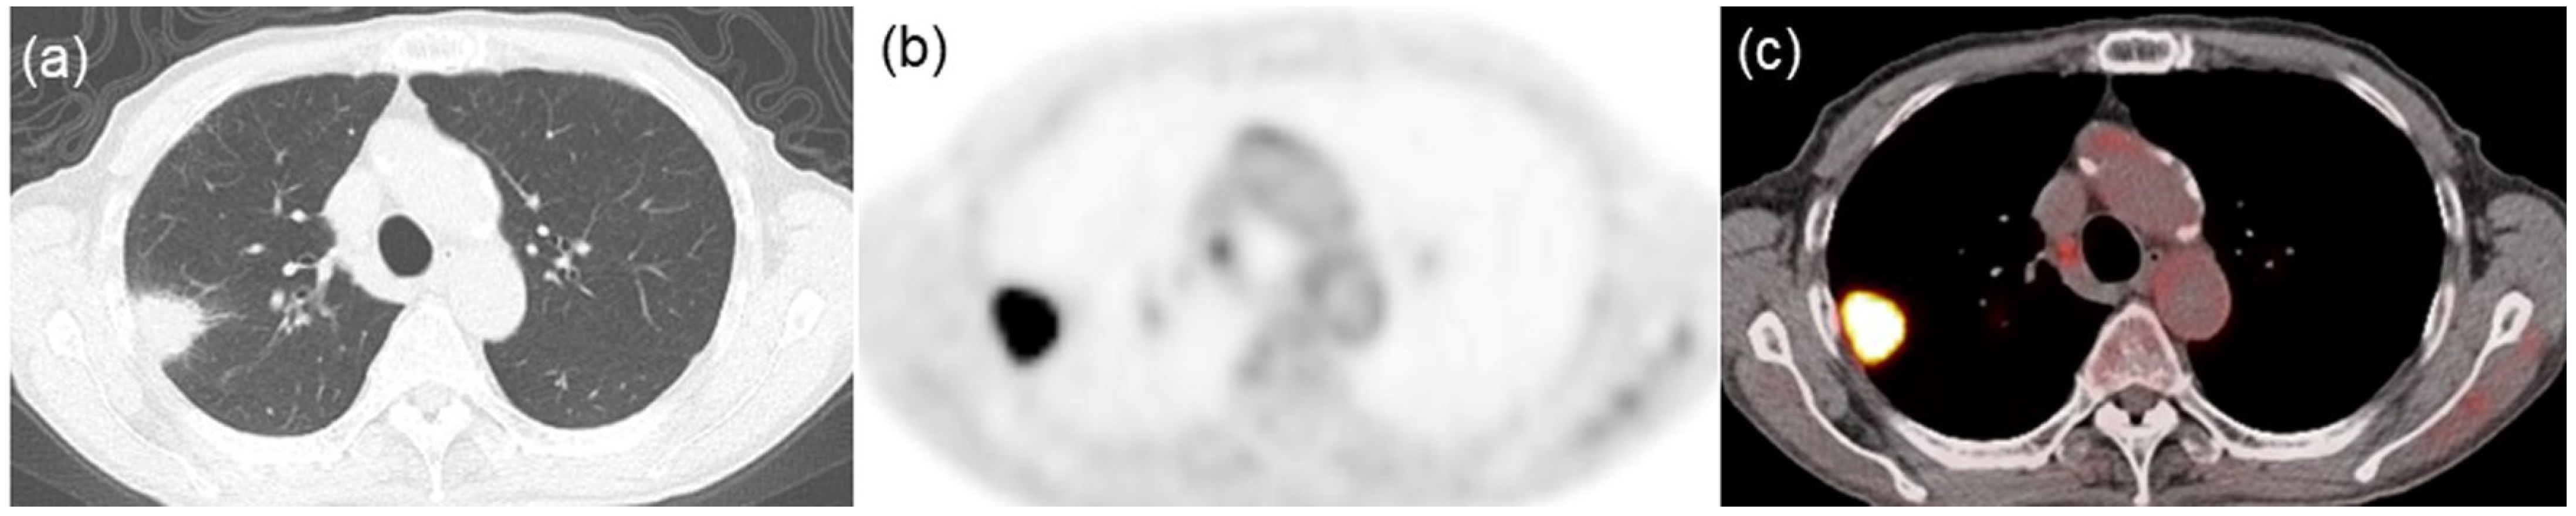

Texture Features of 18F-Fluorodeoxyglucose Positron Emission Tomography for Predicting Programmed Death-Ligand-1 Levels in Non-Small Cell Lung Cancer

2.2. FDG PET/CT Imaging and Analysis